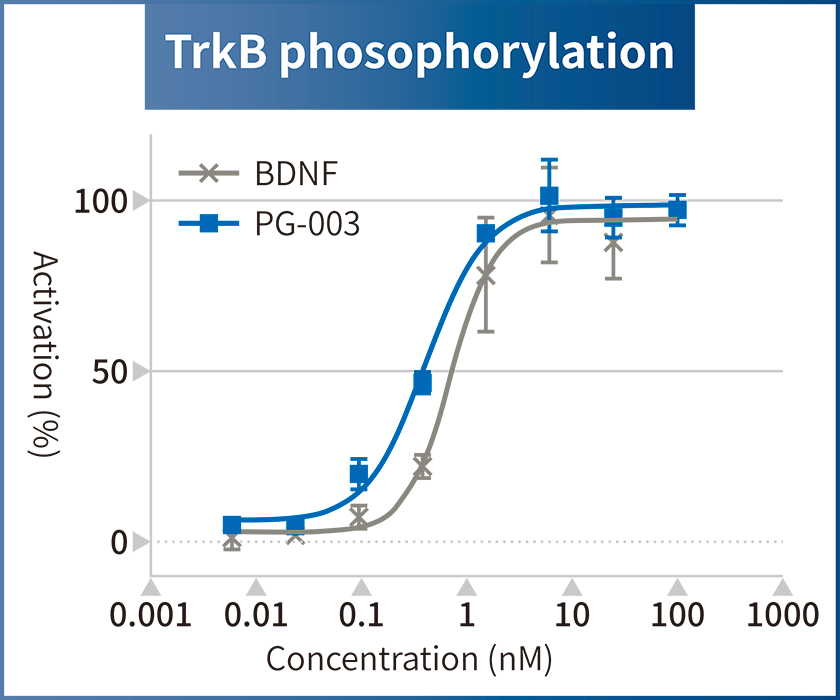

Solve challenges of conventional growth factors

Challenges of conventional growth factors

Currently, FBS and recombinant growth factors are used for cell culture. However, such products have some challenges such as variation in quality among production lots, contamination by biological impurities, low stability, and extremely high prices.